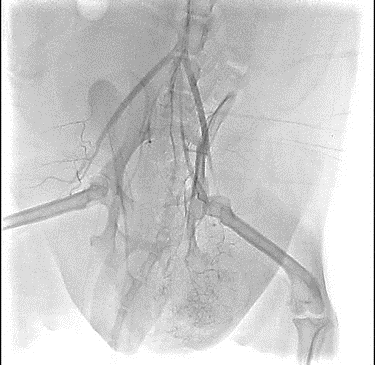

【実施症例】肝臓腫瘍に対する動注療法

柴犬、12歳、雄。

肝臓内側左葉に発生した巨大肝臓腫瘍。高齢で手術リスクが高いため、肝臓腫瘍に対して TACE(肝動注化学塞栓療法)を実施した。 実施から1ヵ月後のエコー検査で、腫瘍の若干の縮小と内部の壊死が認められた。

肝臓腫瘍の3D・CT画像

肝動注化学塞栓療法

実施前

実施後